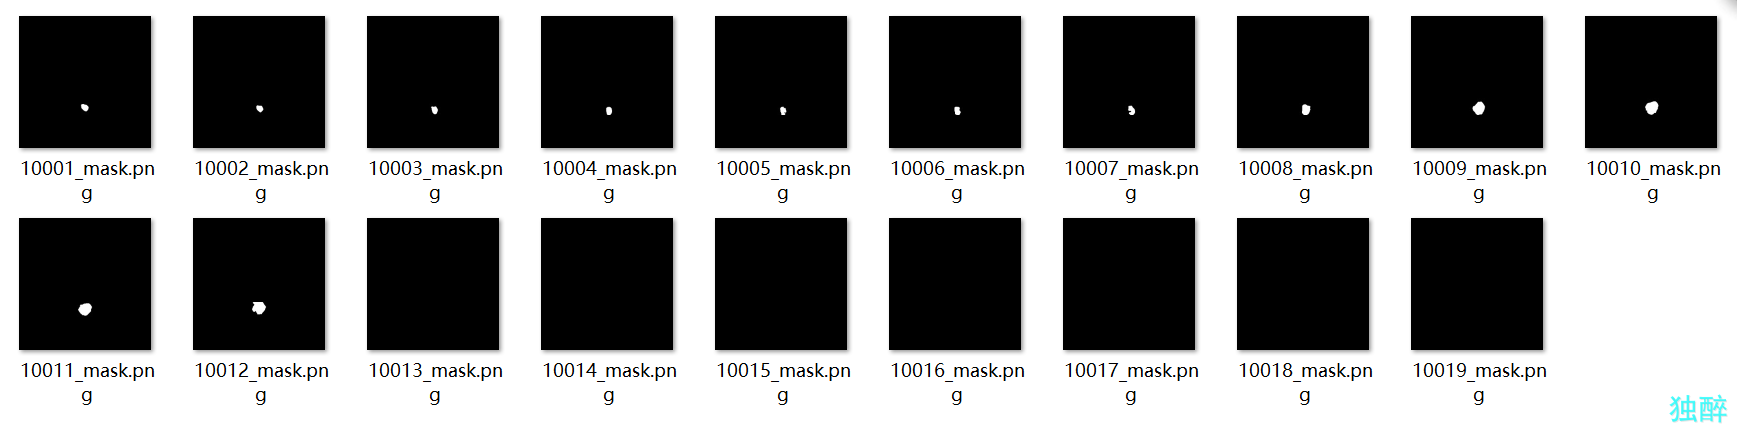

这是掩模图的文件夹,都是png文件,注意相对应的CT图和掩模图再文件夹里的位置一定要对应。

这是掩模图的文件夹,都是png文件,注意相对应的CT图和掩模图再文件夹里的位置一定要对应。